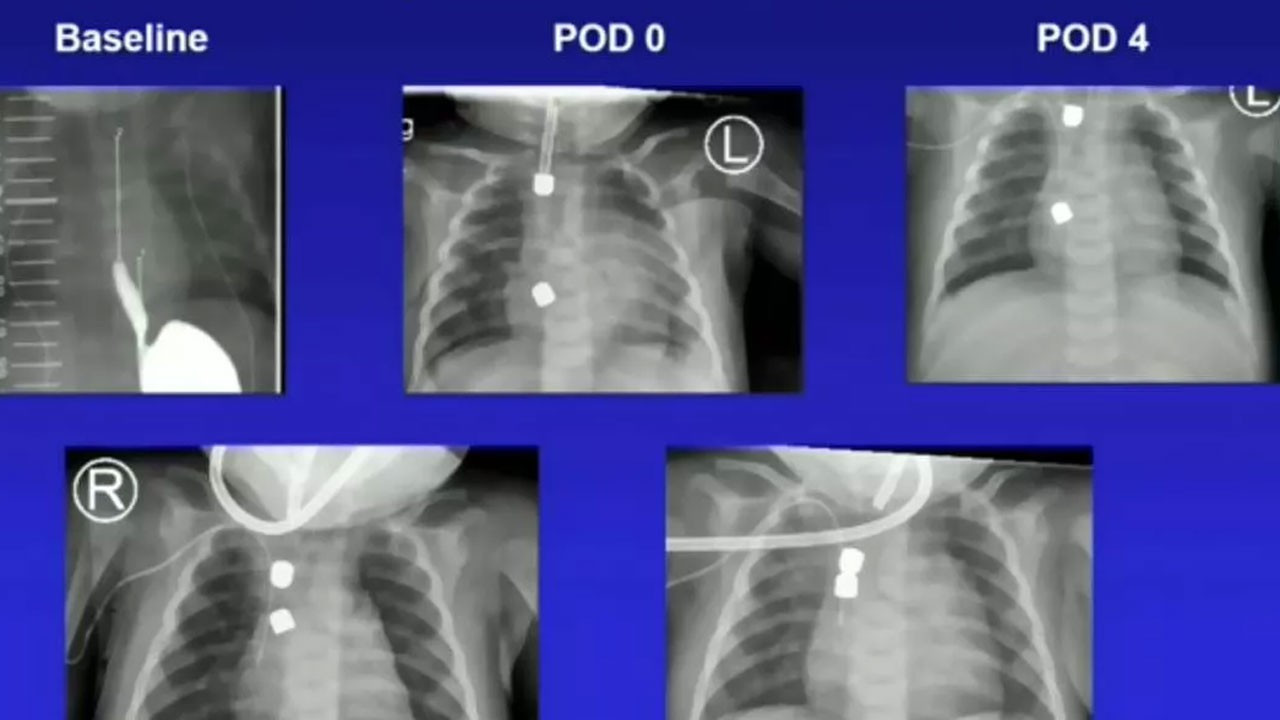

Ameliyat sonrası bir hafta boyunca röntgenlerle kontrol edilen mıknatısların çalışması, Deneen'in ailesini sevince boğdu.